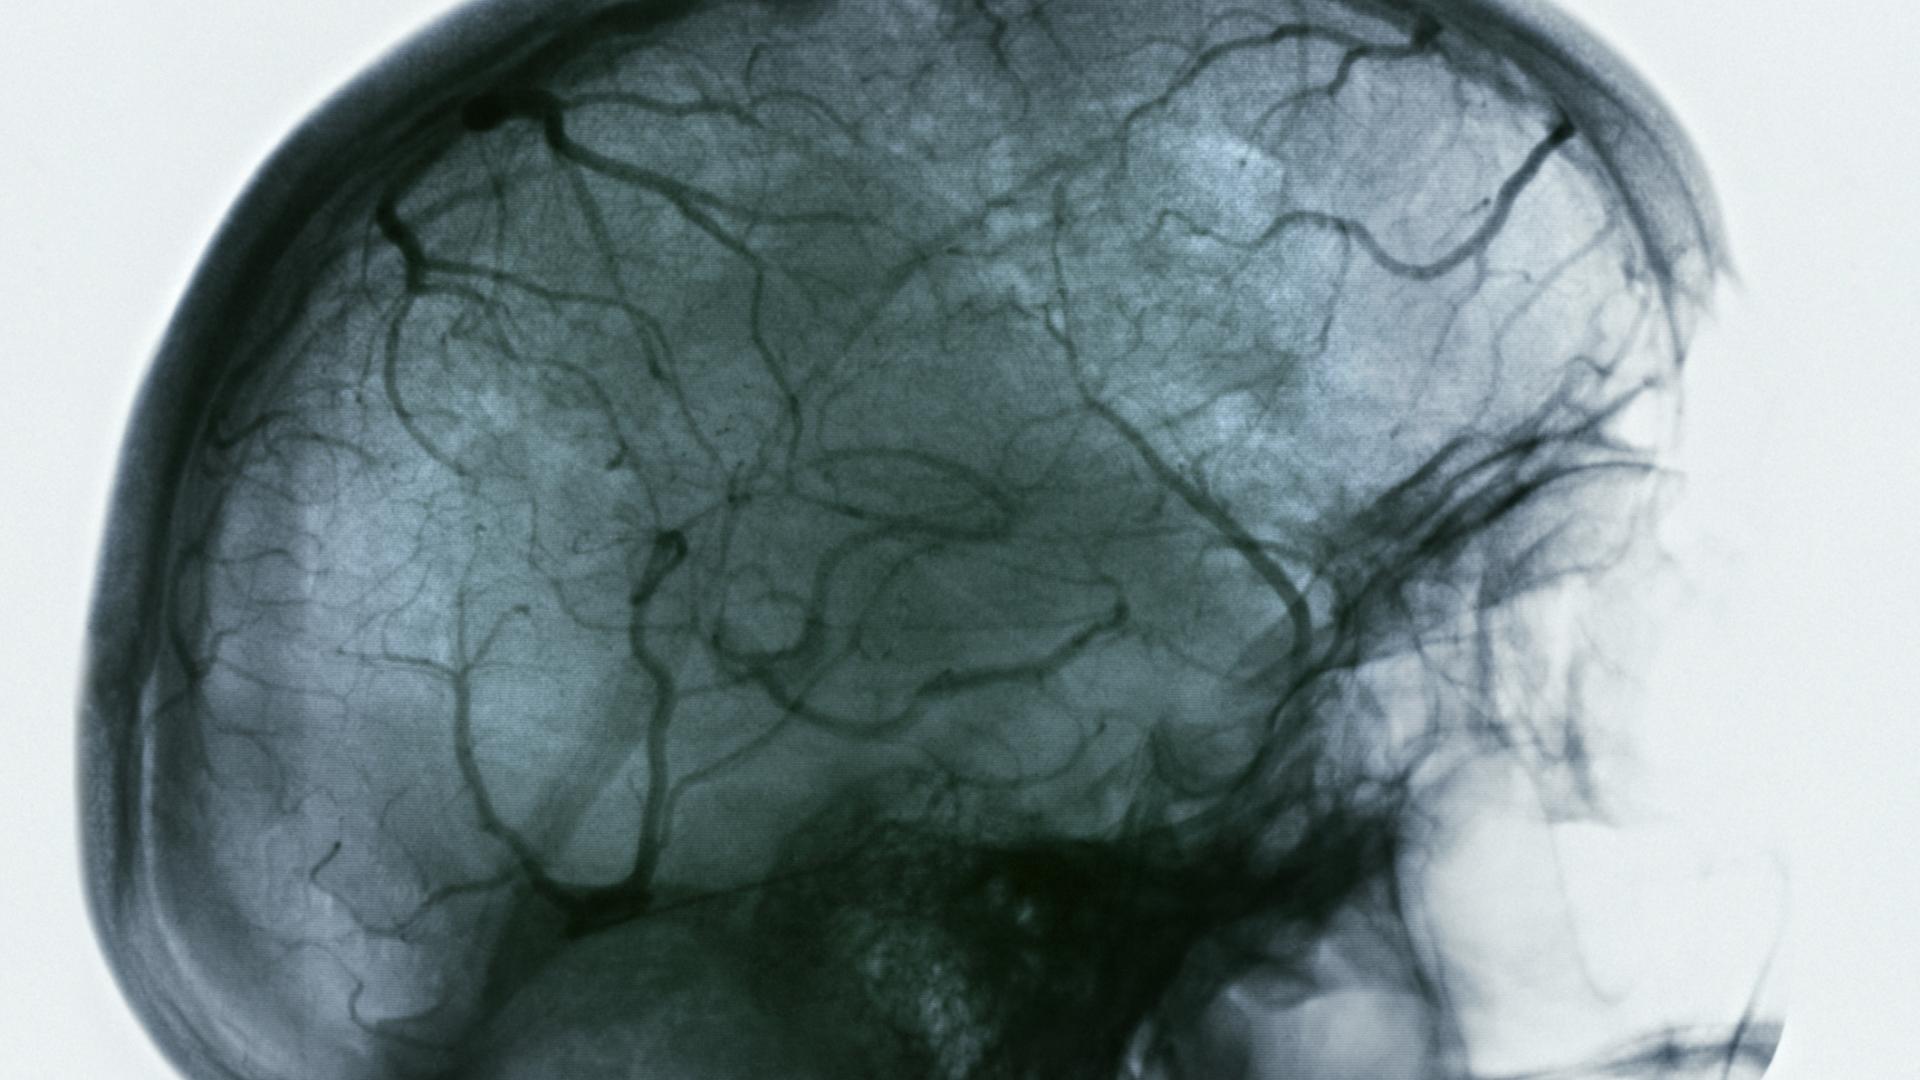

The brain is an energy-demanding tissue requiring nutriment and oxygen, while at the same time needing protection from other potentially harmful agents, for example, viral or bacterial particles which may be delivered by the circulation. For this reason, cells lining the walls of the fine capillaries that supply blood to the brain have tight junctions, which, as the name implies, reduce the space between these cells essentially to zero, forming an exceedingly tight seal. This barrier is termed the blood-brain barrier (BBB) and it performs the essential role of preventing the majority of blood-borne components from gaining access to delicate neural tissues. Here, we will examine how amyloid beta, a peptide that has previously been found to accumulate in the brains of Alzheimer’s disease patients, can exert an impact on the tight junctions and how we may be able to facilitate greater clearance of amyloid-beta from brain blood using a technology termed RNA-interference combined with current antibody-based developmental drugs.